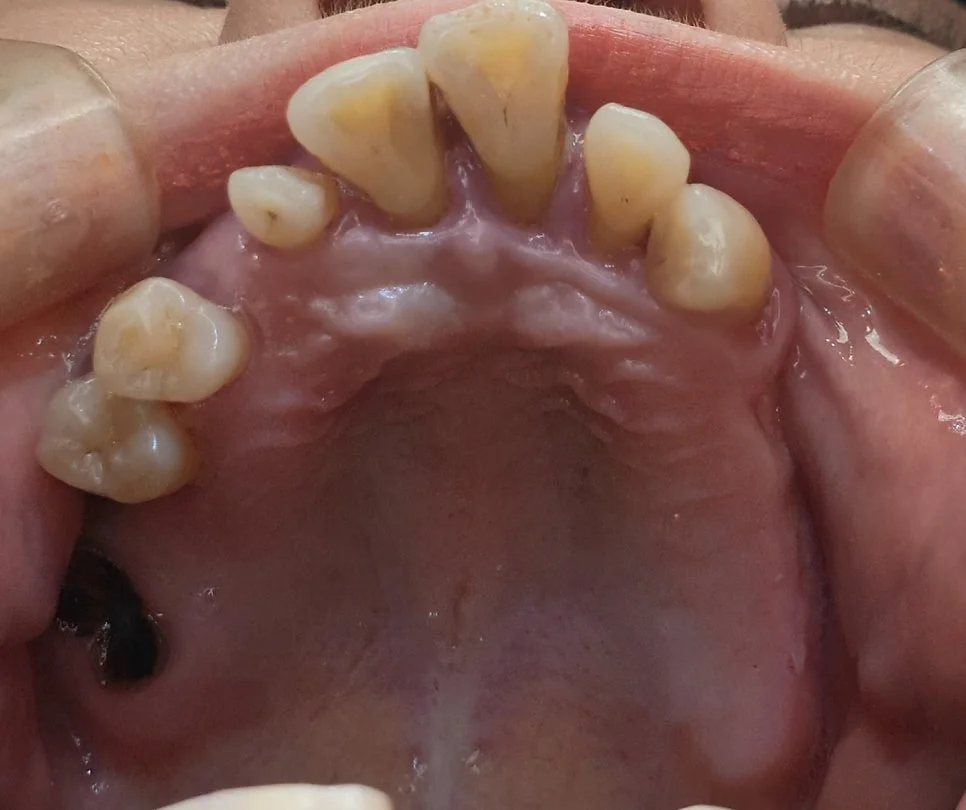

스케일링할 때 착색제거, 지각과민처치, 레진연마까지 받을 수 있을까?

스케일링 전 상악 치아 착색 화살표 표시 증례1

좋은 진료를 정직하게 | 선한 영향력으로 더 나은 가치를 스케일링할 때 착색제거, 지각과민처치, 레진연마까지 받을 수 있을까? 강서구 마곡 서울쏙쏙치과 꿈꾸는 쏙쏙 치과의사 박상억입니다^^ 안녕하세요^^ 오늘은 마곡 치과에서 가장 흔히 하는 진료인 스케일링에 대해 설명드릴까 합니다! 스케일링은 잇몸 상방의 치석을 제거하는 술식을 말하고, 정기적으로 잇몸 관리 차원에서 받는 술식으로 많이들 알고 계실 것 같습니다! 그런데요, … 더 읽기